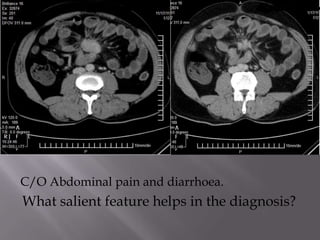

C/O Abdominal pain and diarrhoea.

What salient feature helps in the diagnosis?

DIAGNOSIS; Acute on chronic calcific pancreatitis

with a pseudo cyst in the posterior mediastinum